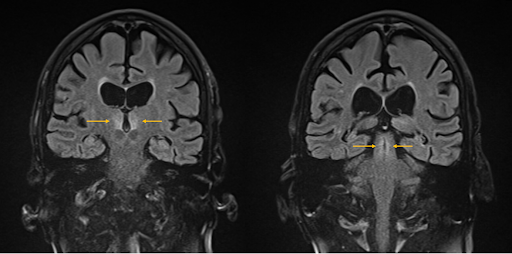

Kopf-MRT

FLAIR-Sequenz: symmetrische hyperintense Signalveränderungen in den Corpora mamillaria sowie in den periventrikulären Bereichen des dritten Ventrikels und des aquäduktalen Mittelhirns.